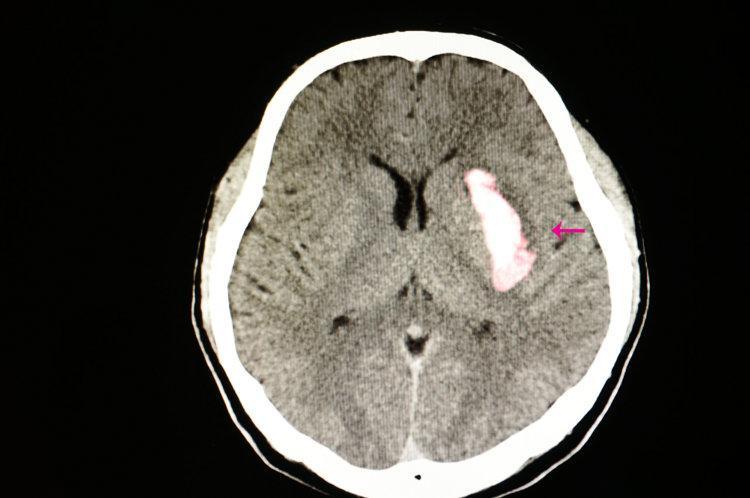

一、長期服用阿司匹林會導致胃出血、腦出血?

因其一方面可以抑制血小板聚集,降低動脈硬化發展的進程,另外一方面也會增加出血事件,尤其是腦出血、胃腸道出血風險。

《JACC》上發表過一項涉及16項合計有17.1萬餘人研究的薈萃分析,經分析發現,相較於服用安慰劑的受試者,阿司匹林用於心腦血管疾病的一級預防,可讓心梗風險下降15%,但同時會增加48%的大出血風險